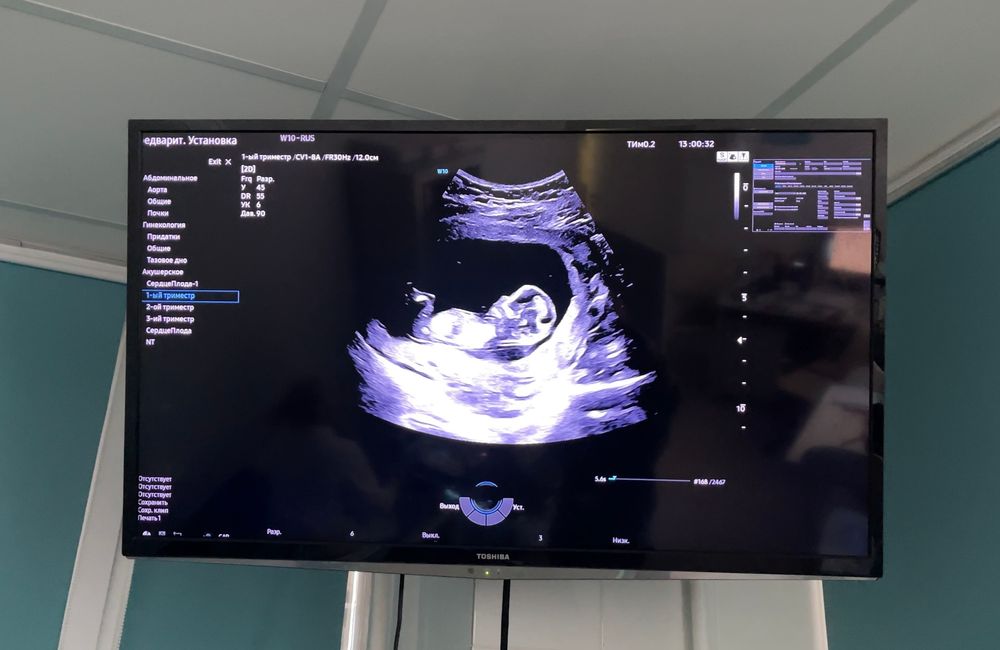

1 скрининг, пол, контракт на ведение 2 триместра и самочувствие